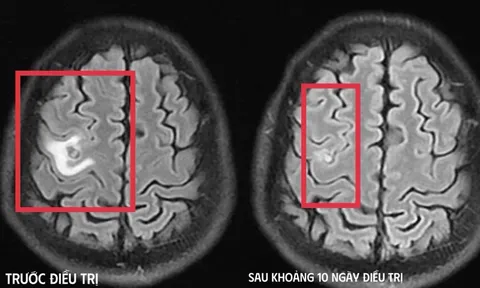

Thông báo dừng hoạt động của K+. Ảnh: K+.